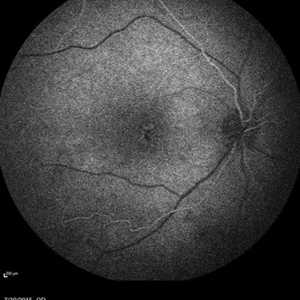

Retinal Dystrophy of 24-Year-Old Male/ Red Free OD

Nov 25 2015 by Zach Dupureur

Fluorescein angiography of a 24-year-old male. Juvenile retinoschisis on OCT. FA shows outer retinal staining. Could be associated with Goldman Farve Syndrome.

Photographer: Zach Dupureur OCT-C

Imaging device: Heidelberg Spectralis

Condition/keywords: Goldmann-Favre Syndrome, juvenile retinoschisis, retinal dystrophy